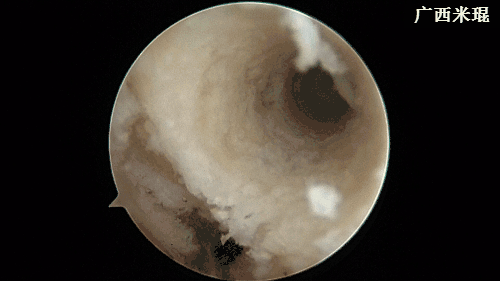

(十七)维合切口

关节镜下检查重建的ACL走向以及张力,屈伸膝关节时观察重建的ACL是否与髁间窝撞击,确认良好后缝合各切口。此过程 一般需要2分钟。